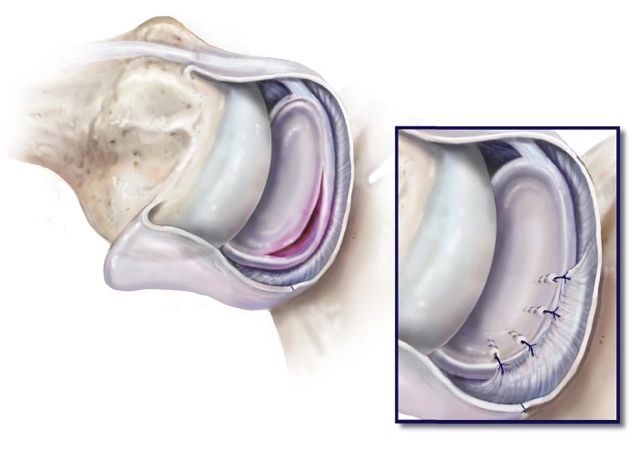

3D planning and personalised guides as part of specilaist shoulder replacement surgery